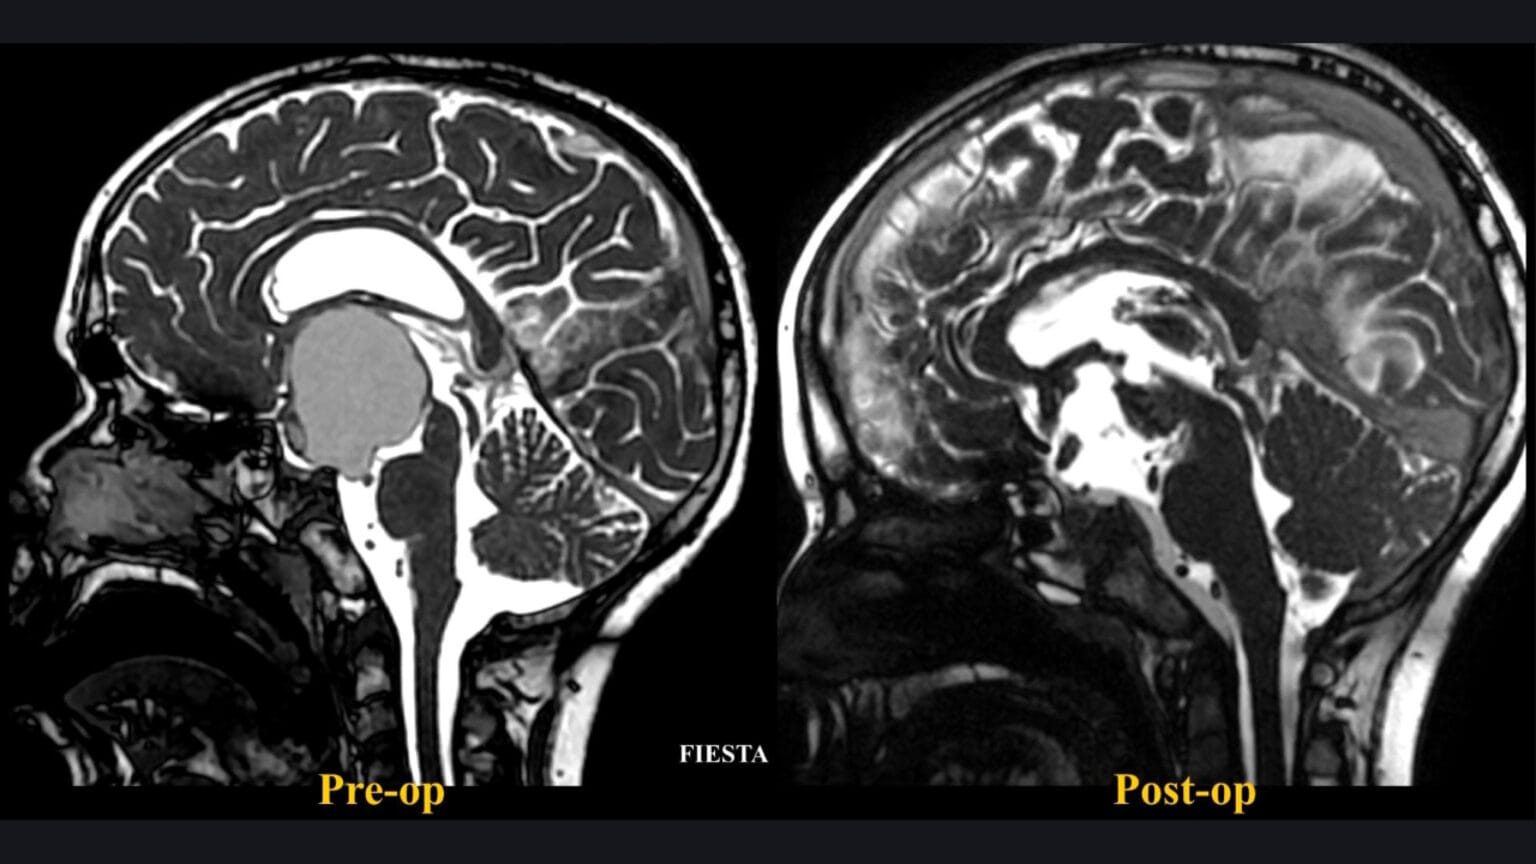

Resección de schwannoma vestibular Koos III guiada con fluoresceína

El prof. Mastronardi realiza la resección microquirúrgica de un schwannoma vestibular Koos III guiada con fluoresceína mediante abordaje retrosigmoideo.